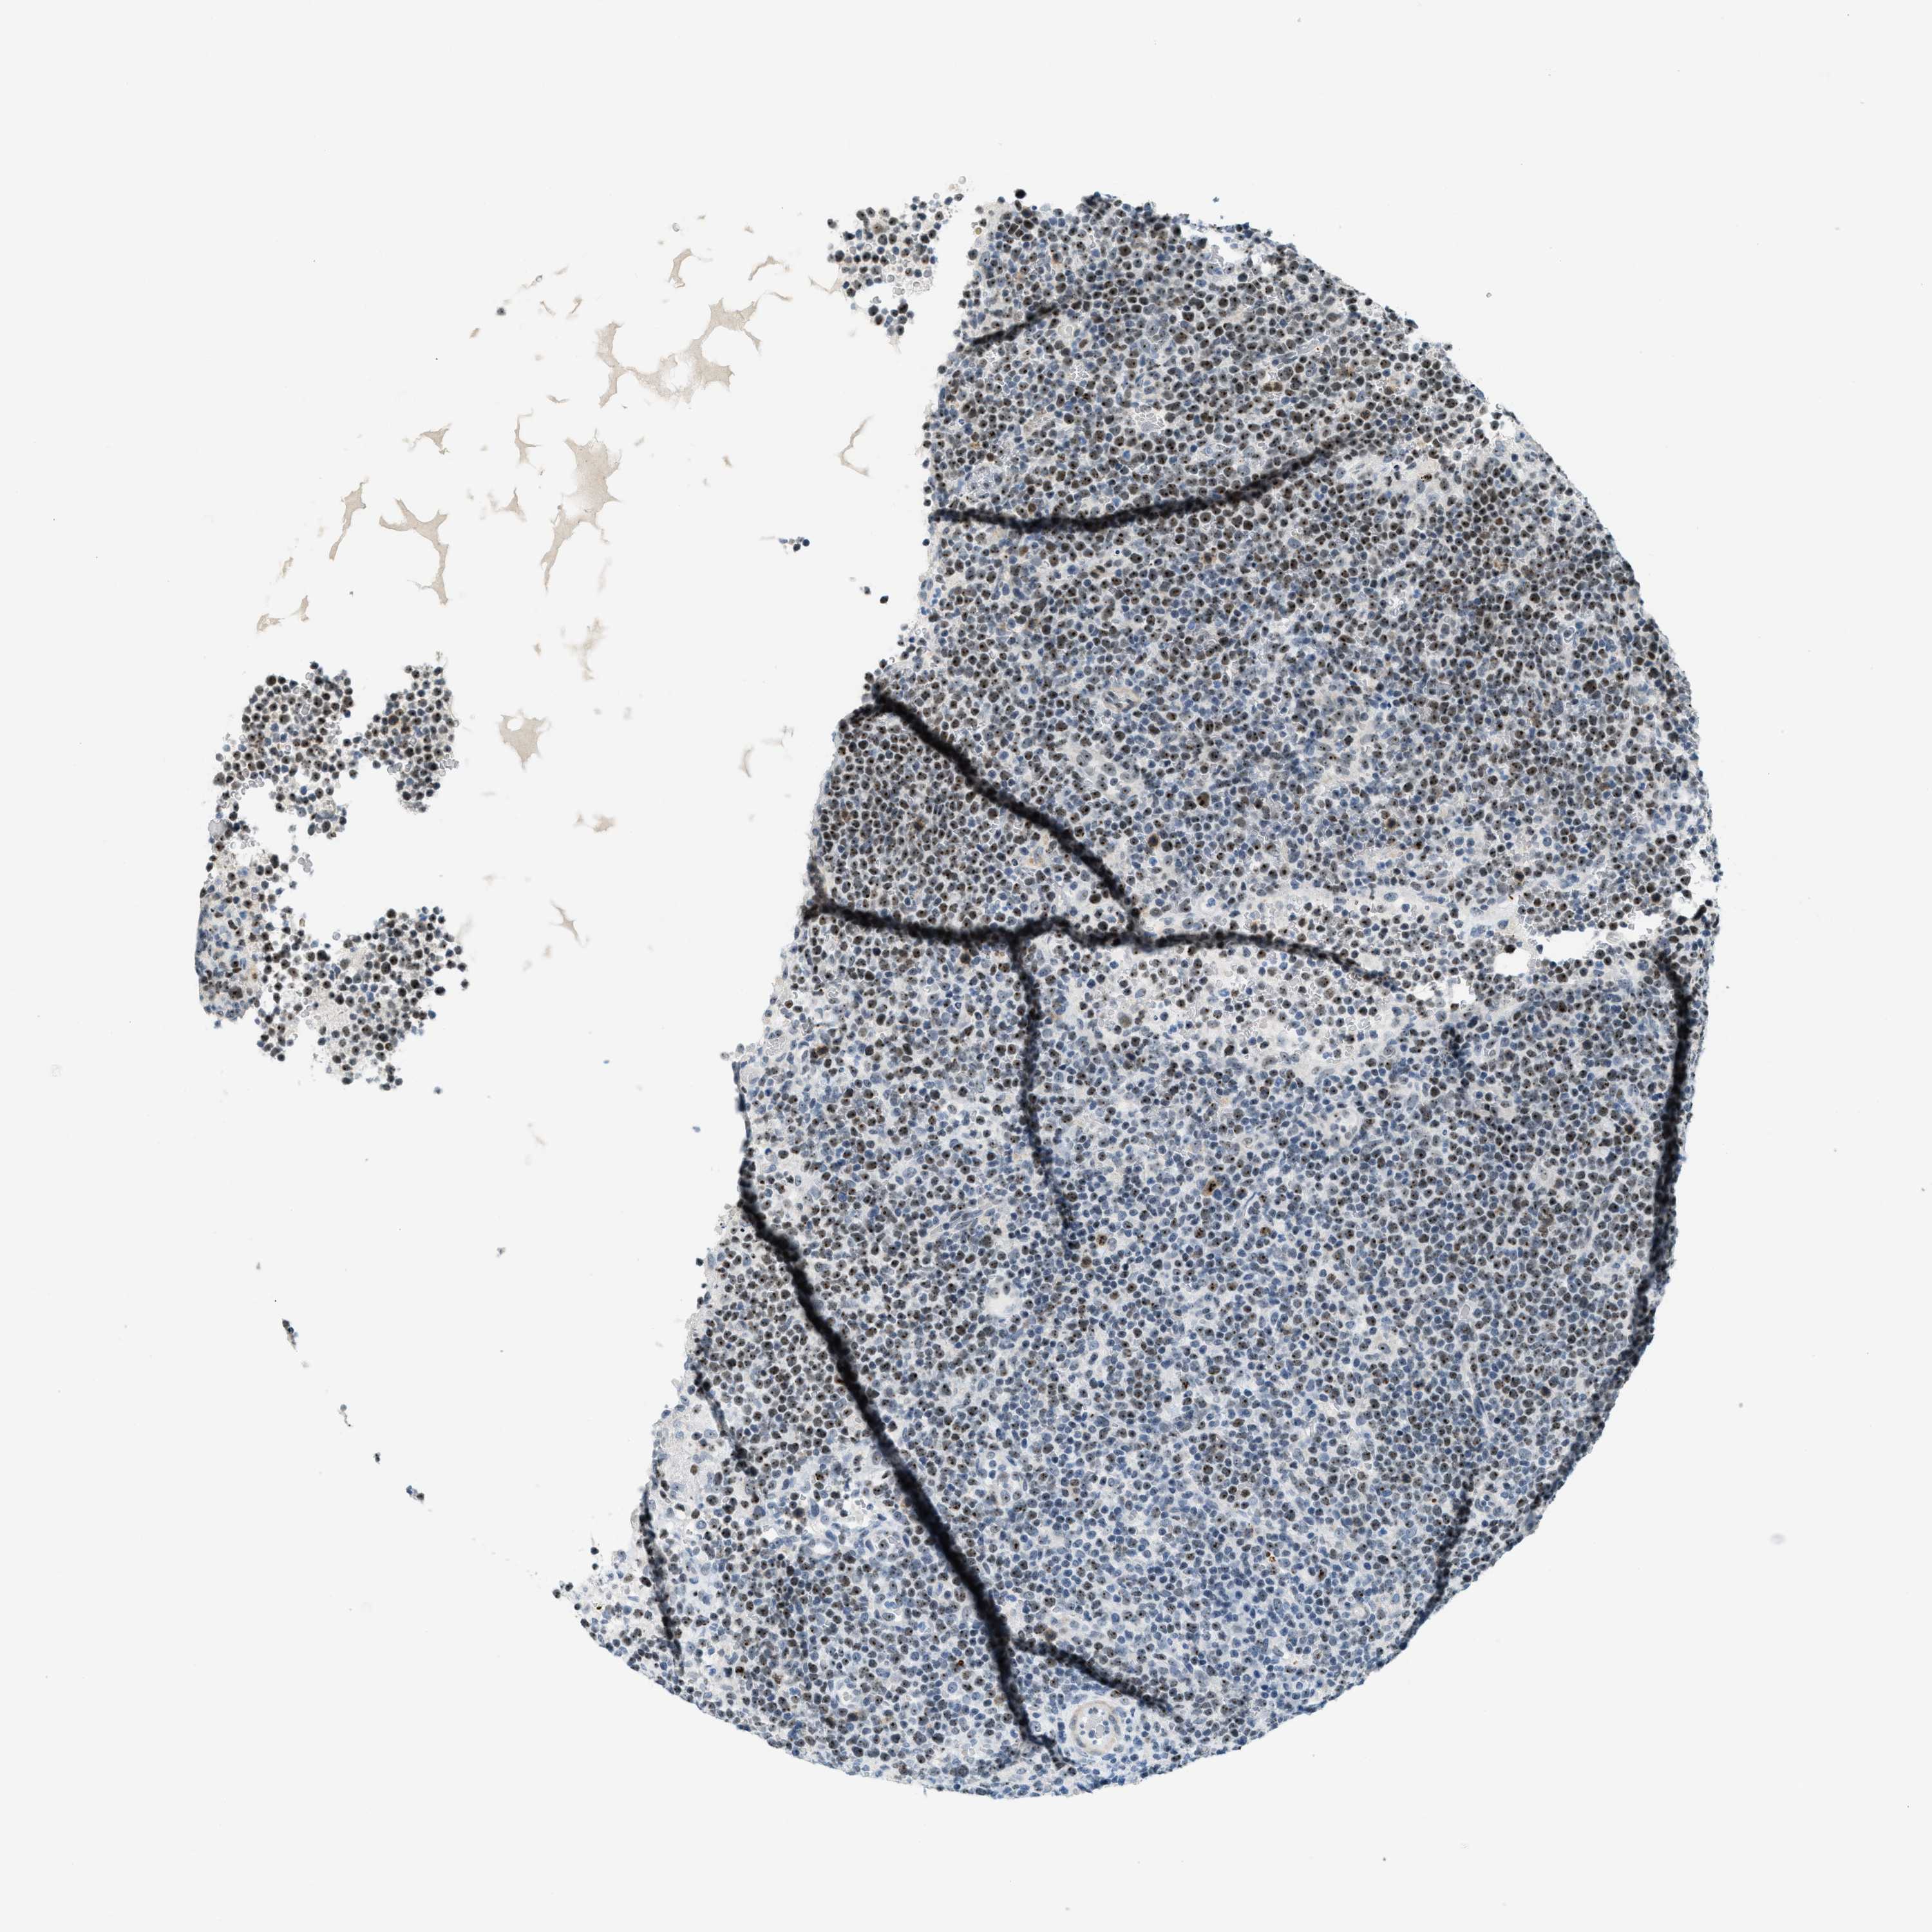

LYMPHOMA - Protein expressioni

A mouse-over function shows sample information and annotation data. Click on an image to view it in a full screen mode. Samples can be filtered based on level of antibody staining by selecting one or several of the following categories: high, medium, low and not detected. The assay and annotation is described here.

Antibody stainingi

Antibody staining in the annotated cell types in the current human tissue is reported as not detected, low, medium, or high, based on conventional immunohistochemistry profiling in selected tissues. This score is based on the combination of the staining intensity and fraction of stained cells.

Each image is clickable and will lead to virtual microscopy that enables deeper exploration of all samples and also displays staining intensity scores, fraction scores and subcellular localization as well as patient and tissue information for each sample.

Antibody HPA014855

Hodgkin's disease, NOS

Malignant lymphoma, non-Hodgkin's type, High grade

Malignant lymphoma, non-Hodgkin's type, Low grade